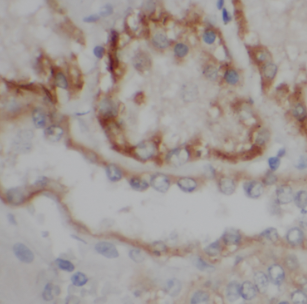

| 验证图片 | Immunohistochemistry of paraffin-embedded human kidney using FNab04900(LY96 antibody) at dilution of 1:50 Immunofluorescent analysis of U2OS cells using FNab04900 (LY96 antibody) at dilution of 1:50 U-937 cells were subjected to SDS PAGE followed by western blot with FNab04900(LY96 antibody) at dilution of 1:400 |